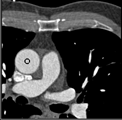

Samples for ascending aorta detection (black circle):

Cluster of candidate points in the ascending aorta.